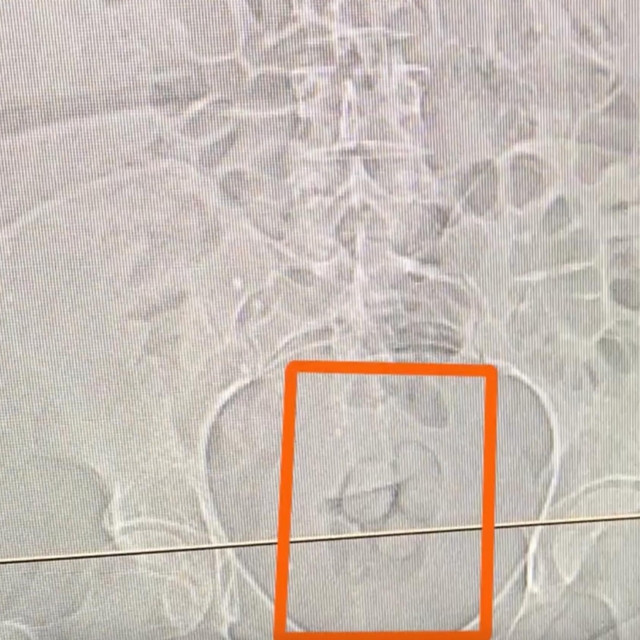

Şüphe üzerine hastaneye götürülen S.S'nin çekilen tomografi görüntülerinde, mide ve bağırsaklarında yabancı cisim olduğu tespit edildi.

S.S'nin yuttuğu 21,39 gram sentetik uyuşturucu, tıbbi müdahaleyle mide ve bağırsaklarından çıkarıldı.